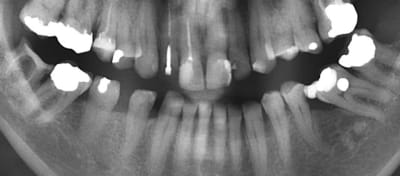

Pourquoi ça se passe comme ça?

Ici ex des 46 36. La 37 se couche tandis que la 47 reste en place et les 45, 44 s'offrent une croisière distale.